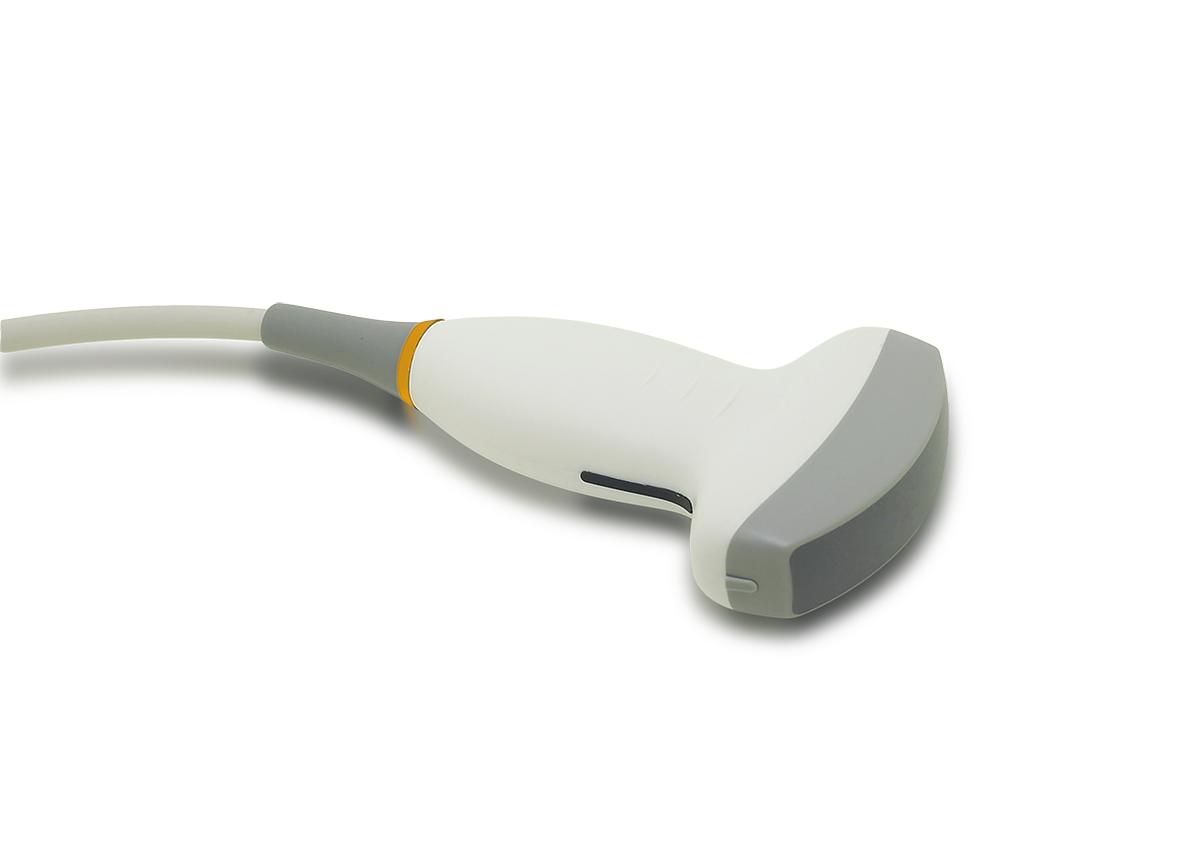

1. Next generation ultrasound transducer

4. Comfort and modern Ergonomic Design